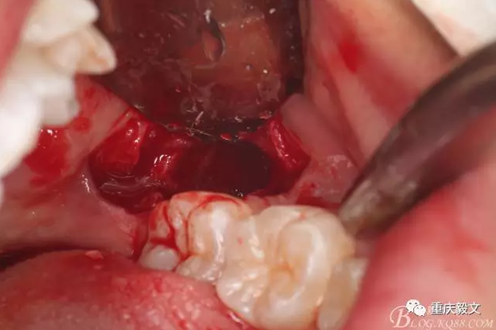

圖6.去骨要點:去除骨組織阻力。視牙齒周圍骨阻力的多少而定去骨量,以暴露牙齒的外形高點線為宜。高速牙鉆去骨,以頰側(cè)去骨為主,遠(yuǎn)中可少量去骨。舌側(cè)禁止去骨。

圖7.縱分牙冠,分牙要點:盡量多分牙、少去骨。根據(jù)牙根分布情況,來決定是縱分、斜分、還是橫分。